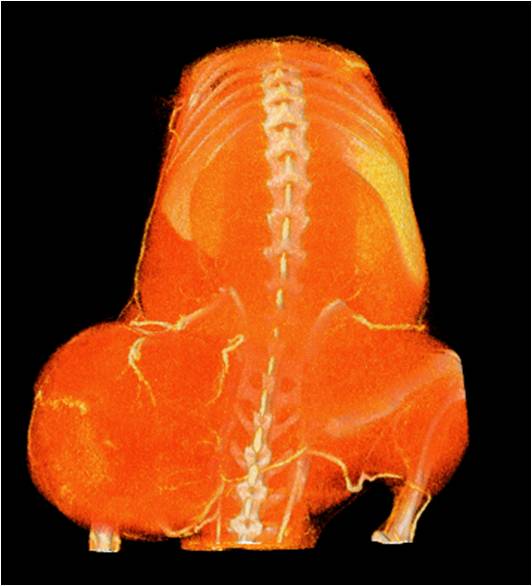

能進行全身血管成像研究,獲得高分辨率的血管造影影像;

能進行肝、脾、腎等內臟的成像研究,獲得體積、表面積等定量參數。